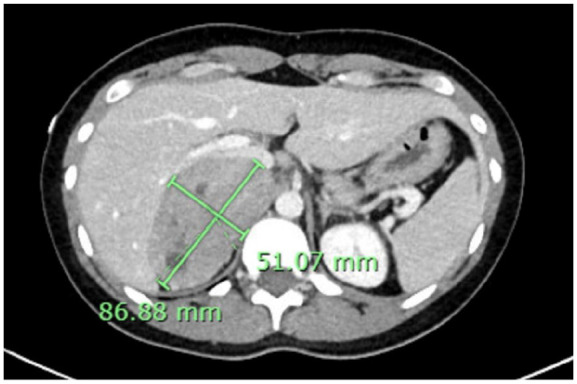

巨大嗜铬细胞瘤是一种罕见的肿瘤,通常超过7厘米。大部分是非儿茶酚胺因肿瘤坏死和结缔组织内容物而分泌。其表现可以从典型的肾上腺素能亢进症状到模糊的胃肠道不适。较大的肿瘤有较高的转移风险、死亡率和围手术期并发症。我们的病例是一位31岁女性,主诉为呕吐,伴有间歇性心悸和血压升高,随后影像学显示右侧肾上腺肿块8.7 cm。完全切除肿物显示一个10 × 7 × 3.9 cm的肿物,占据整个肾上腺髓质,符合巨大嗜铬细胞瘤。本病例为支持微创方法和个体化治疗巨嗜铬细胞瘤提供了证据。此外,它强调了在症状模糊的情况下高度临床怀疑的重要性。

Giant pheochromocytomas are rare tumors, typically exceeding 7 cm in size. Most are noncatecholamine secreting due to tumor necrosis and connective tissue content. Their presentation can range from classic hyperadrenergic symptoms to vague gastrointestinal complaints. Larger tumors are associated with higher risks of metastasis, mortality, and perioperative complications. Our case presents a 31-year-old female who presented with the chief complaint of vomiting, associated with intermittent palpitations and elevated blood pressure, with subsequent imaging revealing an 8.7 cm right adrenal mass. Complete resection of the mass showed a 10 × 7 × 3.9 cm mass that occupied the entire adrenal medulla, consistent with a giant pheochromocytoma. This case contributes to the evidence supporting a minimally invasive approach as well as individualized management of giant pheochromocytomas. Furthermore, it emphasizes the importance of a high clinical suspicion in the context of vague symptoms.